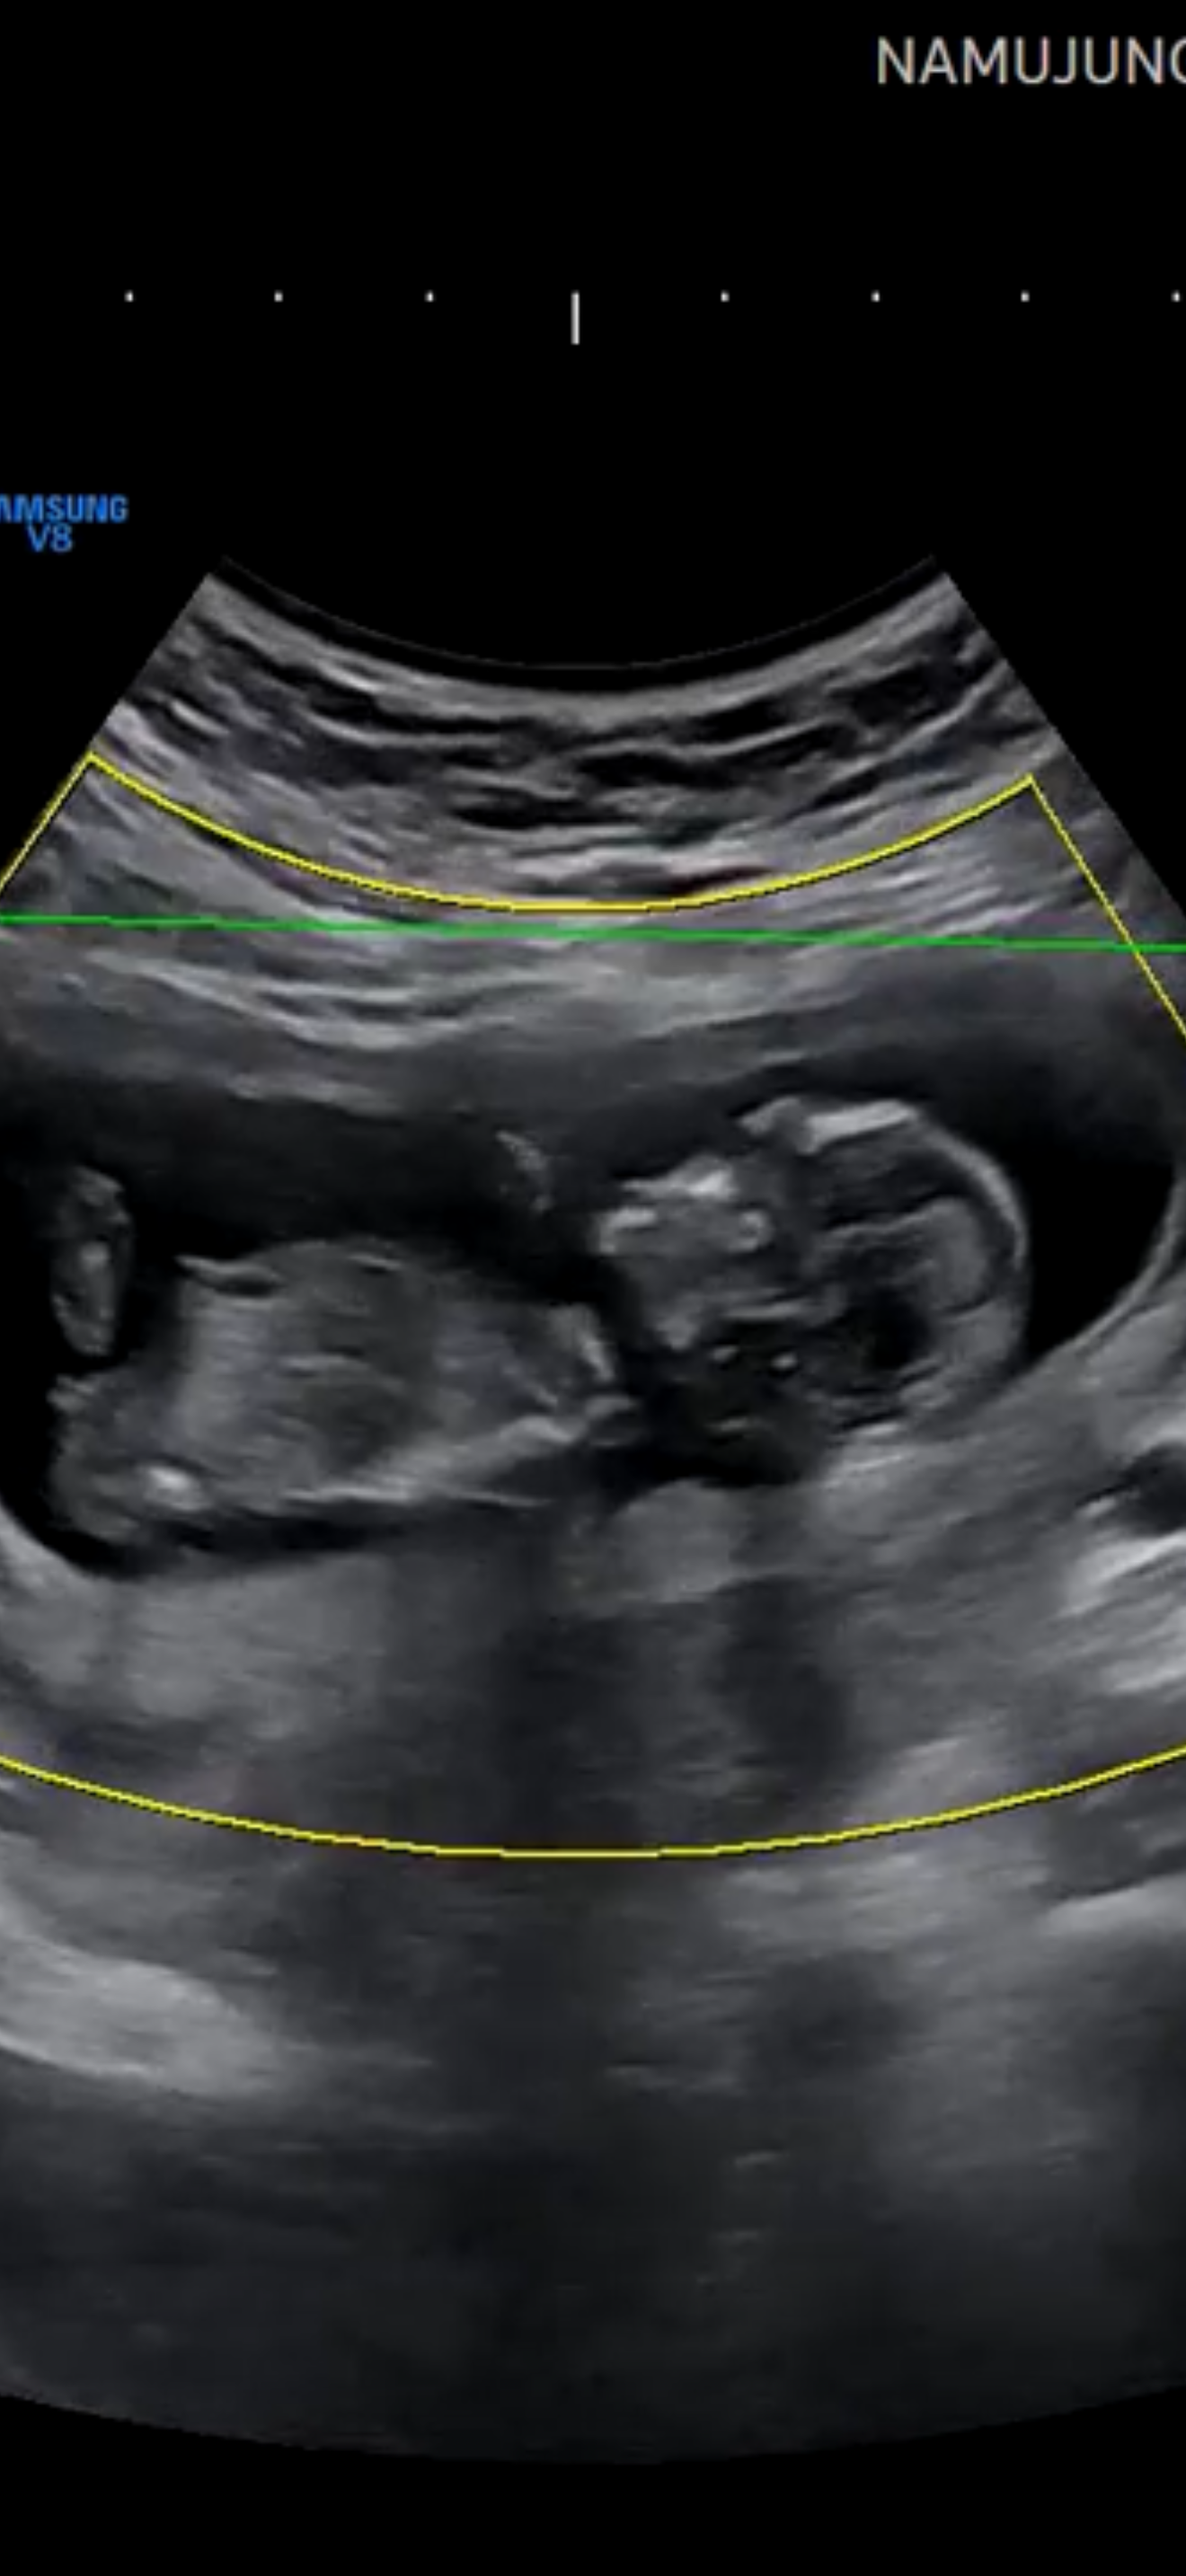

고수님들 12주 각도법 봐주세요🩷❤

12주 때 초음파인데 너무너무 궁금해 미쳐가는 중이에요ㅎㅎㅎ첫째가 아들이거든요 아들 너무 예쁘고 사랑스러운데 제가 체력이 안되서 이번에는 순둥한 딸을 낳고싶어요 물론 딸이라고해서 다그런건아니지만 그저 얌전하고 순둥하다면 아들도 좋아요 ㅠㅠ 둘째로 끝내려고해서 이왕가진김에 딸이었으면 좋겠어여 ㅠㅠㅠㅠ ---------------------추가글------------------------- 딸이었습니다!